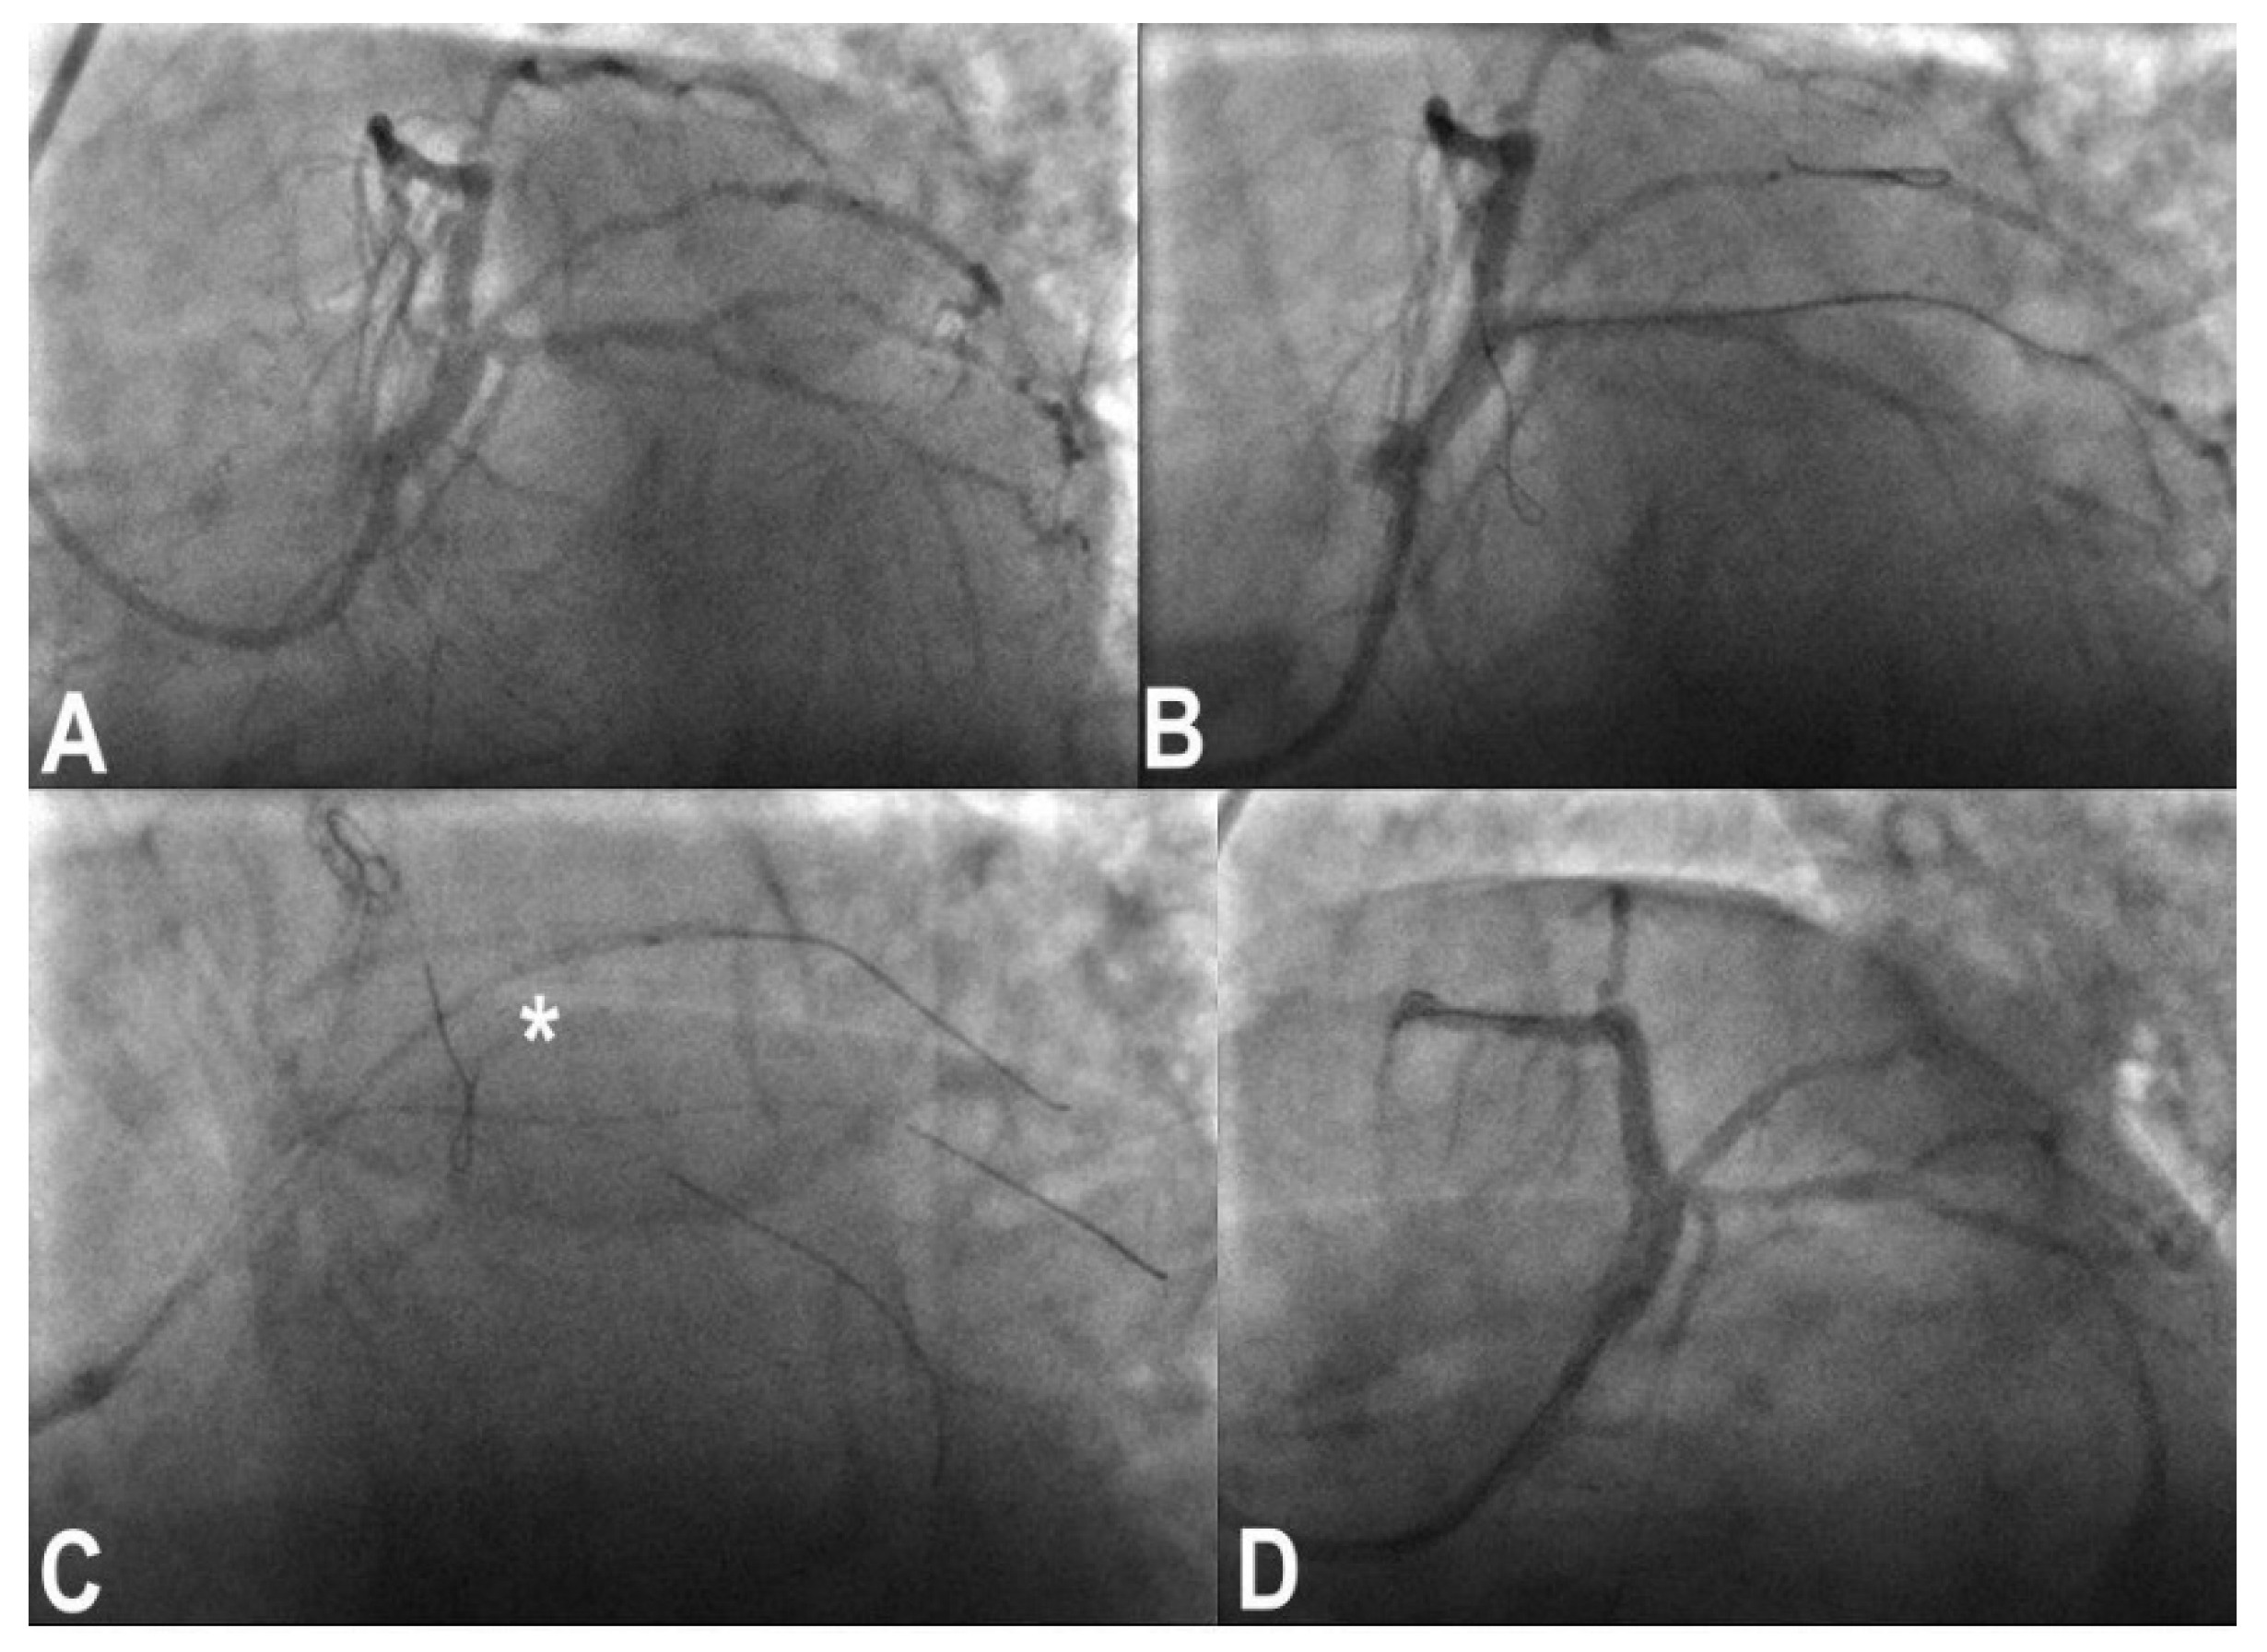

3.7. Wire Entrapment and Fracture

- Li, C.; Chen, Z.; Wang, M. Retrieving entrapped guidewire using rotablation technique: Case series and literature review. Eur. Heart J. Case Rep. 2022, 6, ytac261. [Google Scholar] [CrossRef] [PubMed]